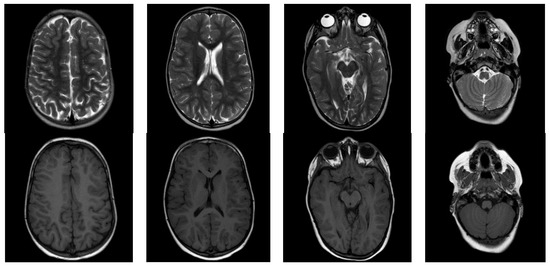

3.1. Case Report